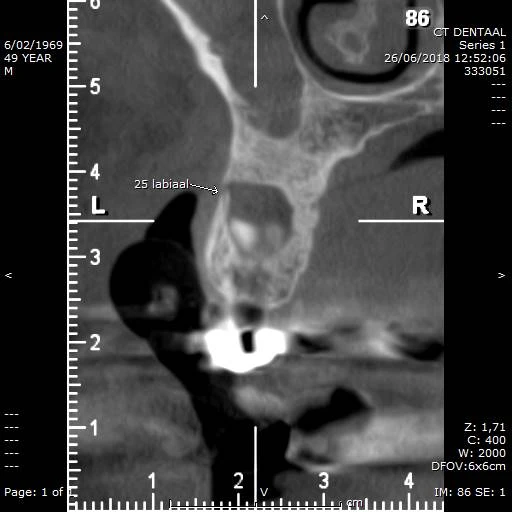

Ingesloten wijsheidstand maxillair (M3) met infectie, sinusitis én botdoorbraak labiaal

CBCT voorbeeld 1: sagittale doorsnede

Sagittale doorsnede: 25 labiaal, sinus maxillaris betrokken